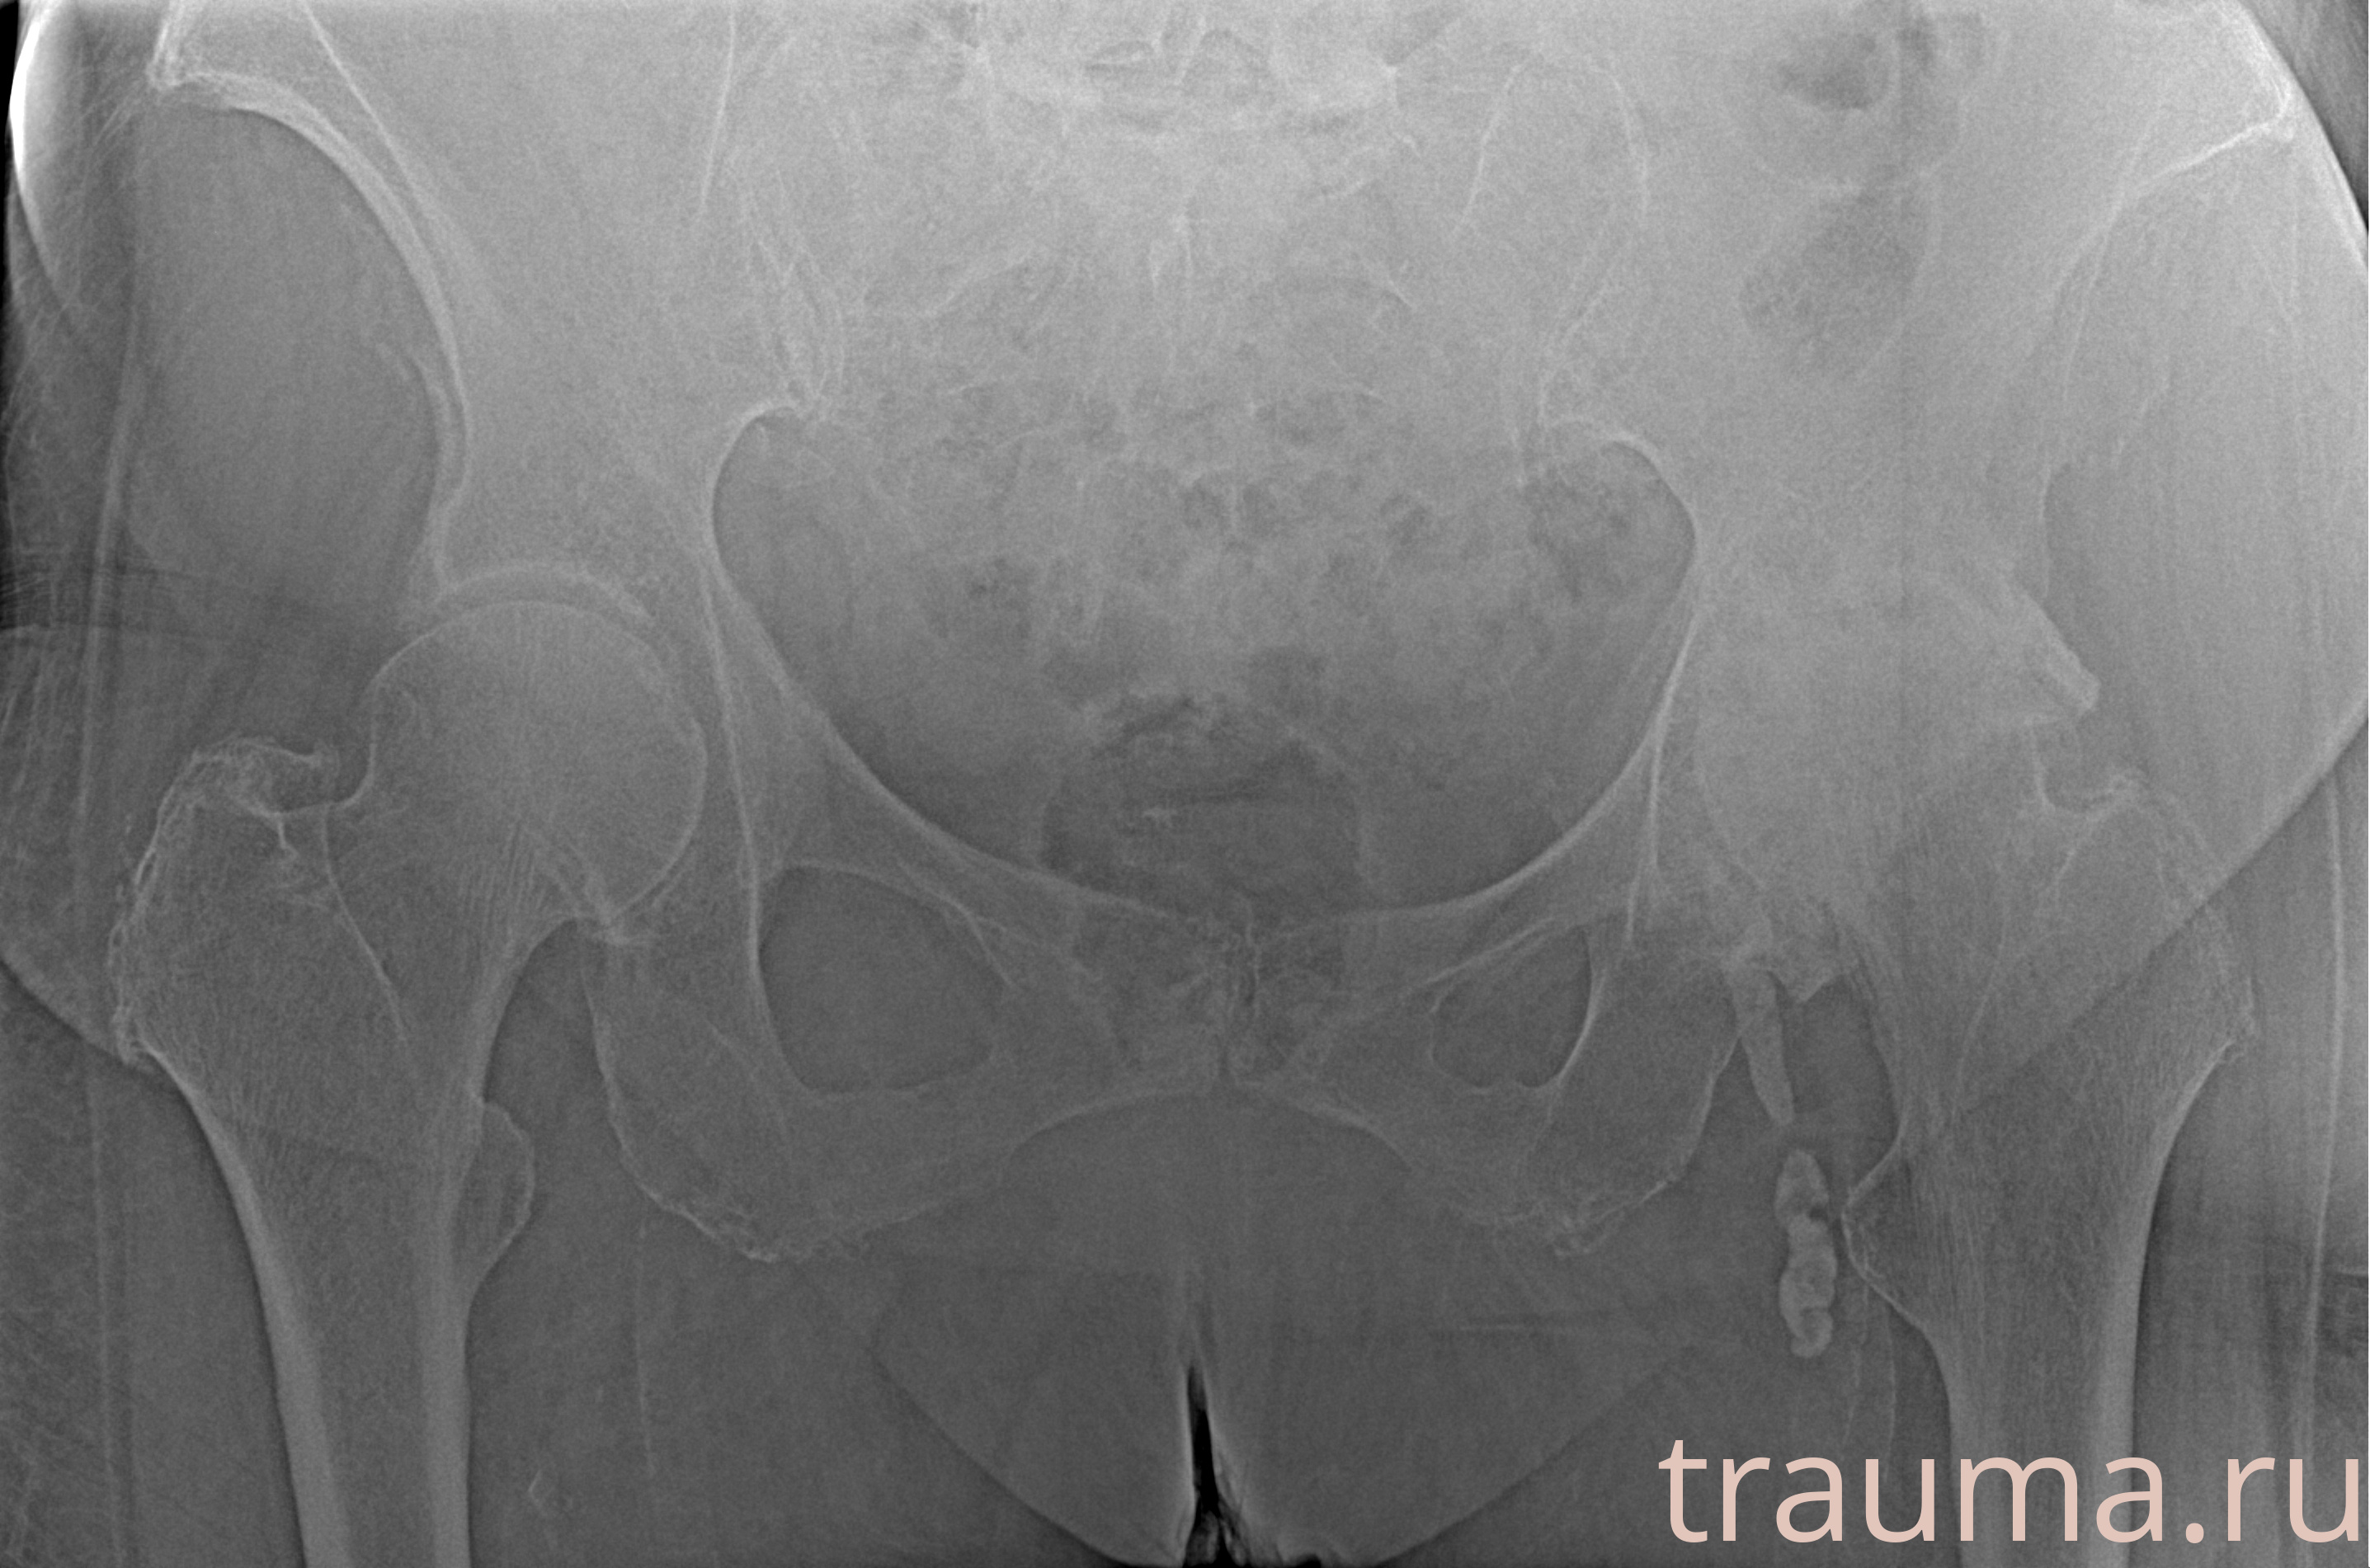

Рентгенограммы

Рентген на дому: по вашему адресу приезжает врач-рентгенолог, травматолог-ортопед с мобильным рентгеновским аппаратом, проводит диагностику травмы или заболевания, делает необходимые рентгенограммы, дает рекомендации по дальнейшему лечению. Получить качественные снимки в домашних условиях возможно благодаря уникальной методике, разработанной МосРентген Центром для института  Склифосовского

при переломе шейки бедра и пневмонии от компании МосРентген Центр - партнера Института имени Склифосовского